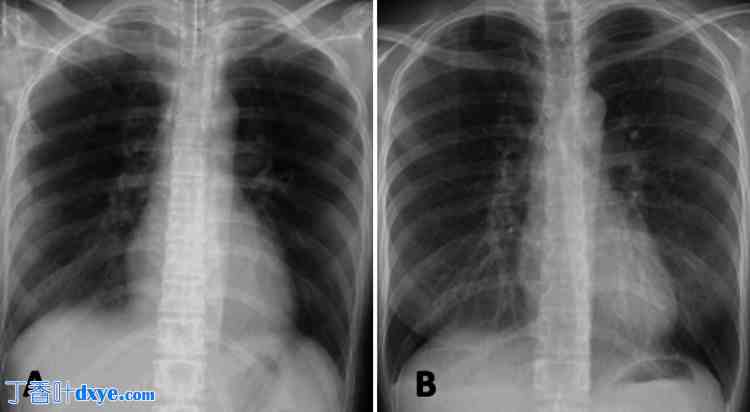

图2. 术后胸片。

(A) 术后第1天 (POD):经机械通气和利尿治疗后,肺水肿明显改善。 (B)POD 4:肺部检查结果几乎恢复正常。